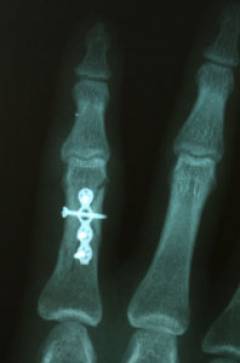

Открытая репозиция

Этот метод лечения применяется при переломах пальцев как крайняя мера. Открытая репозиция — это хирургическое вмешательство, связанное с воздействием на открытую кость. Как и любая операция, она может вызвать осложнения: инфицирование раны, нарушение швов, остеомиелит и другие. Однако в некоторых случаях этот метод становится единственным вариантом лечения. Обычно это открытые простые или многооскольчатые переломы с смещением, неправильно сросшиеся переломы, требующие повторной репозиции, и гнойные осложнения после других методов лечения.

Процедура выполняется по стандартам хирургического вмешательства под общим наркозом. Фиксация костных отломков чаще всего осуществляется с помощью спиц, реже — шурупов. Также возможно использование аппарата внешней фиксации, известного как аппарат Илизарова. Его преимущество — надежная фиксация без гипса, что помогает избежать запаривания раны и предотвращает инфекции. Однако аппарат требует тщательной ежедневной обработки, так как является инородным телом и может вызвать воспаление.

Остеосинтез с использованием спиц и шурупов может быть одно- или двухэтапным. При одноэтапном остеосинтезе фиксационные элементы остаются в кости на всю жизнь, а при двухэтапном их удаляют через 3-4 недели с помощью миниинвазивного вмешательства. В результате, восстановительный период составляет 4-6 недель при одноэтапном и 7-8 недель при двухэтапном остеосинтезе.